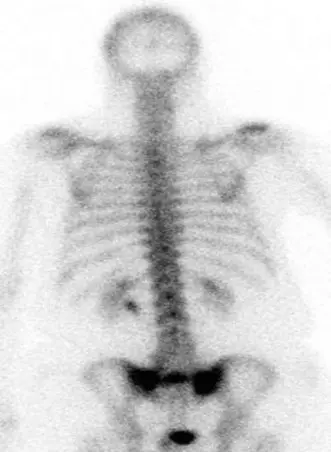

التصوير بالرنين المغناطيسي (MRI):

- يُعتبر المعيار الذهبي لتشخيص كسور العجزية القصورية عندما تكون الأشعة السينية العادية سلبية.

- يُظهر التصوير بالرنين المغناطيسي بوضوح وذمة نخاع العظم (التي تظهر كإشارة منخفضة في صور T1 وإشارة عالية في صور T2/STIR)، وهي علامة مميزة لكسر حاد أو شبه حاد، حتى قبل ظهور خط كسر واضح في التصوير المقطعي.

- يُمكنه أيضًا تقييم إصابات الأنسجة الرخوة والضغط على الأعصاب.

صورة بالرنين المغناطيسي نموذجية تُظهر وذمة نخاع العظم المتوافقة مع كسر العجزية القصورية. تُبرز الإشارة العالية في تسلسلات STIR خط الكسر الذي غالبًا ما يكون خفيًا في الأشعة السينية العادية. -